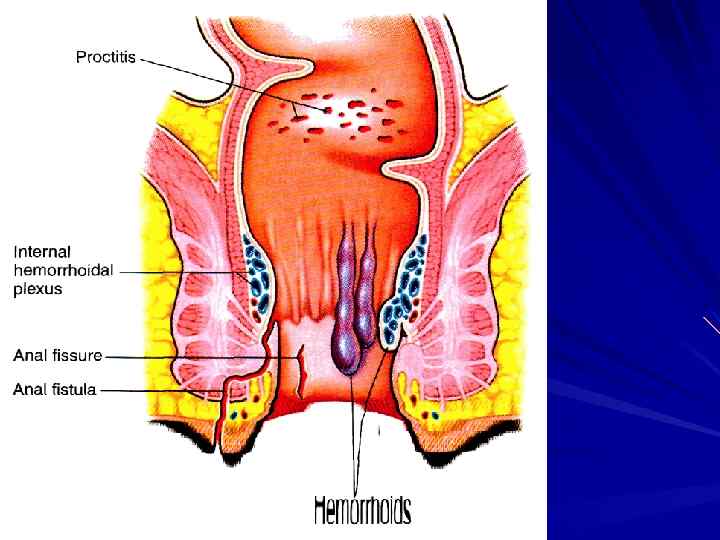

ДЕФЕКАЦИЯ КАЛ – гл. обр. в СИГМОВИДНОЙ КИШКЕ СЛАБЫЙ СФИНКТЕР и ОСТРЫЙ УГОЛ ПОПАДАНИЕ КАЛА в RECTUM → ПОЗЫВ КАЛ = 80 – 200 мл

ДЕФЕКАЦИЯ КАЛ – гл. обр. в СИГМОВИДНОЙ КИШКЕ СЛАБЫЙ СФИНКТЕР и ОСТРЫЙ УГОЛ ПОПАДАНИЕ КАЛА в RECTUM → ПОЗЫВ КАЛ = 80 – 200 мл

СФИНКТЕРЫ RECTUM ВНУТРЕННИЙ – ГЛАДКИЕ МЫШЦЫ НАРУЖНЫЙ – ПОПЕРЕЧНОПОЛОСАТЫЕ МЫШЦЫ (СРАМНОЙ НЕРВ)

СФИНКТЕРЫ RECTUM ВНУТРЕННИЙ – ГЛАДКИЕ МЫШЦЫ НАРУЖНЫЙ – ПОПЕРЕЧНОПОЛОСАТЫЕ МЫШЦЫ (СРАМНОЙ НЕРВ)

ПОПАДАНИЕ КАЛА в RECTUM → МЕЖМЫШЕЧНОЕ СПЛЕТЕНИЕ → СИГМА → ↑ПЕРИСТАЛЬТИКИ И РАССЛАБЛЕНИЕ ВНУТРЕННЕГО СФИНКТЕРА PS-РЕФЛЕКС

ПОПАДАНИЕ КАЛА в RECTUM → МЕЖМЫШЕЧНОЕ СПЛЕТЕНИЕ → СИГМА → ↑ПЕРИСТАЛЬТИКИ И РАССЛАБЛЕНИЕ ВНУТРЕННЕГО СФИНКТЕРА PS-РЕФЛЕКС

СПОСОБСТВУЮТ ДЕФЕКАЦИИ НАПРЯЖЕНИЕ БРЮШНОЙ СТЕНКИ ЗАДЕРЖКА ДЫХАНИЯ ЗАКРЫТИЕ ГОЛОСОВОЙ ЩЕЛИ

СПОСОБСТВУЮТ ДЕФЕКАЦИИ НАПРЯЖЕНИЕ БРЮШНОЙ СТЕНКИ ЗАДЕРЖКА ДЫХАНИЯ ЗАКРЫТИЕ ГОЛОСОВОЙ ЩЕЛИ